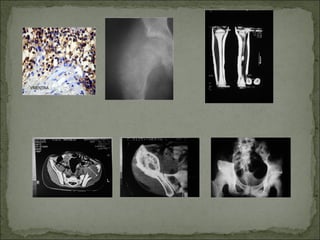

Tumor maligno caracterizado por la formación directa

de tejido óseo u osteoide por las células madres.

Luego del mieloma, es el tumor óseo primario

maligno más frecuente.

Edad más frecuente: 2 ª década (62%)

Sexo: varones (60%)

Localización: áreas metafisarias de rodilla (>fémur

).

Dolor

Masa palpable

Signos locales inflamatorios y éstasis venoso

Deterioro del estado gral.

Metafisario (en pacientes con cartílago abierto separa a la

epífisis-discutible para algunos), central

Osteolítico (a veces mezclados con zonas densas:

rarefacción)

Imágenes más comunes:rayo de sol, triángulo de Codman,

lámina de cebolla (más del t. de Ewing)

Fx patológicas ( más raro)

 Tumor agresivo localmente caracterizado por numerosas células gigantes del tipo

osteoclástico.

 Frecuencia: 8% de todos los tumores óseos.

 Edad: 4° década

 Sexo: mujeres 65%

 Localización:Rodilla ( fémur y Tibia), extremo inferior de radio

 Clínica: dolor y tumefacción

 Rx: epifisario y excéntrico, radiolúcida.

 Tto: curetaje más cemento o injerto óseo, con o sin fenolización

 Resección en bloque

 Nunca radioterapia (fibrosarcoma, ostesarcomas)

 Frecuencia: 9% de los tumores óseos malignos.

 Edad: 1ª década

 Sexo: varones ligeramente más.

 Localización: diáfisis de huesos largos.

 Síntomas:dolor, masa palpable, circulación colateral, deterioro del estado gral.

 Rx: esclerosis ósea, imagen en catáfilas de cebolla o de rayo de sol.

 Tto: radioterapia

quimioterapia

Qx

Pronóstico: depende del diagnóstico precoz y del estado gral.